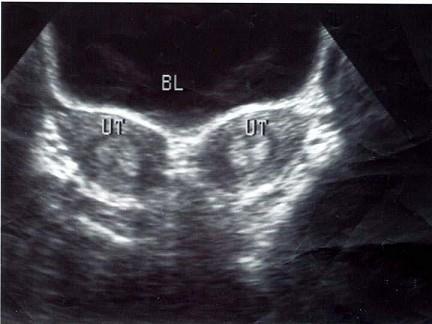

女性,25岁,婚前妇科体检。超声检查如图,最可能的诊断为?(?)A.畸胎瘤B.盆腔血肿C.子宫浆膜下肌瘤D.双子宫E.双角子宫

问题 女性,25岁,婚前妇科体检。超声检查如图,最可能的诊断为?(?)

选项 A.畸胎瘤 B.盆腔血肿 C.子宫浆膜下肌瘤 D.双子宫 E.双角子宫

答案 D